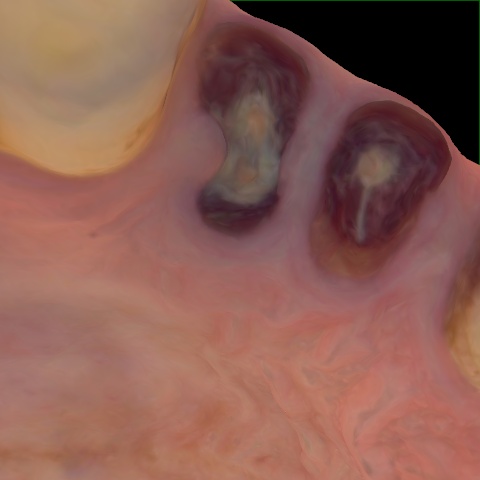

Original Image Rendering Image